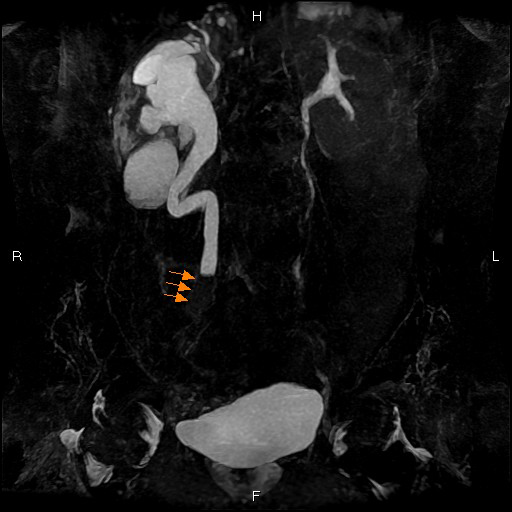

非造影による管腔構造描出

造影剤を使用することなく、非侵襲的に有用な情報が得られます。

<腎動脈狭窄症>

<尿管腫瘍>

<閉塞性動脈硬化症>心臓のMRI